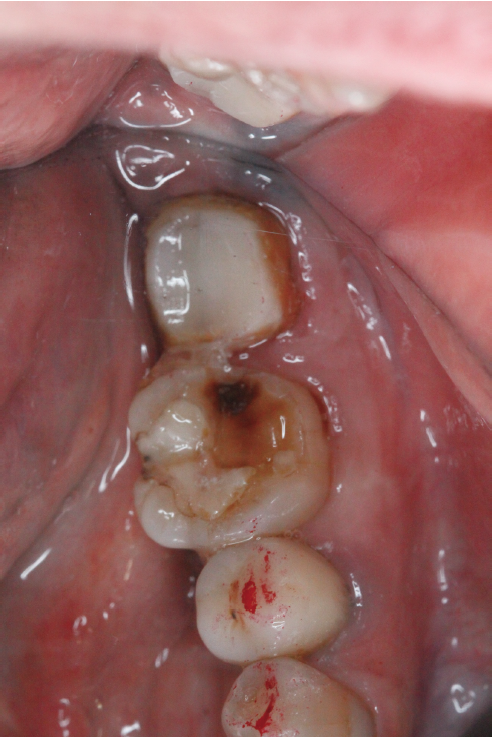

当院に来院される患者さんの多くは『他院で抜くしかないと言われる歯をなんとか残して欲しい』と言う希望の元来られます。現在歯を失う大きな原因となっている3大原因は『虫歯、歯周病、破折』です。多くは虫歯や破折なのですがこう言った歯の場合の治療には根管治療が必要になることがほとんどです。根管治療とは簡単に言うと、『ラバーダム』(写真1)と言われるゴムのカバーを歯に取り付け、根っこの中にある汚れを隅々まで取り、できる限り無菌に近い状態にして最後に蓋をする、と言う一連の流れになります。そしてその際に根っこの中にヒビが見つかったり根っこの中からのお掃除では綺麗になりきらず治癒しない場合は再植と言う治療になります。再植は『一回歯を抜いてお口の外でその歯を治療し再びお口の中に戻す』と言うものです。(写真2)『抜いた歯を再び植える』と言うことで再植と言う名がついています、他の方法で違う場所から歯を持ってきて(移動してきて)植える事を『移植』と呼んだりしてます。こちらの移植の方が臓器等、医科の分野でも使われる技術なので皆様には馴染みがあるかもしれませんね。

そしてこの再植と言う治療に入ると歯を一旦抜くことによって一時的に歯は弱まるのでしっかり休めなければなりません、期間はその歯の状態や個々の回復の差によりますが基本的には4ヶ月程休ませてあげます。その4ヶ月の間歯は噛ませることなくそっとしておくのですがその待っている間に『土台』を建てます。(写真3)この土台に関しては当会の会報誌でもまだ説明したことがないのでいずれ紹介しようと思っています。この土台の治療とは根っこの治療が終わった歯にするもので根っこに再度菌が入り込みにくくする、歯を割れにくくする、などの意味があります。